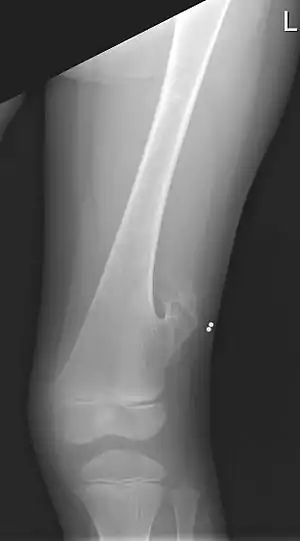

| X-ray of the left femur of a 5-year-old boy with an exostosis at the lateral side, just above the knee. | |